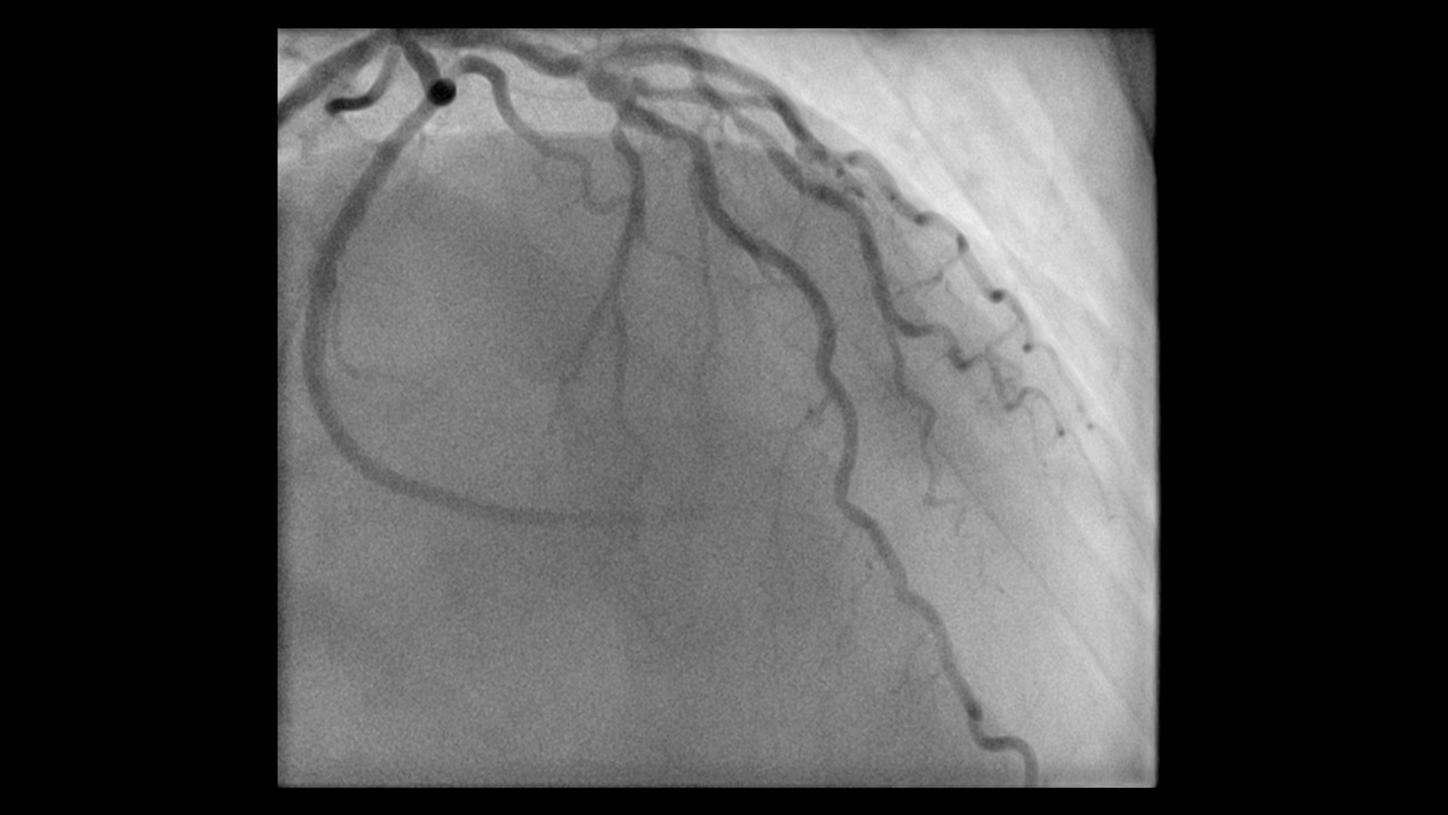

During minimally invasive procedures, it is critical to have a clear view of anatomies and devices. Yet complex imaging tasks or challenging patient conditions often impact image quality. OPTIQ AI delivers constant image quality1 defined by CNR in support of the ALARA principle, independent of patient or C-arm angulation. On top, an AI-powered algorithm reduces image noise in real time across different 2D imaging modes.

Make AI-powered imaging and clear insights your standard during interventions – with OPTIQ AI.